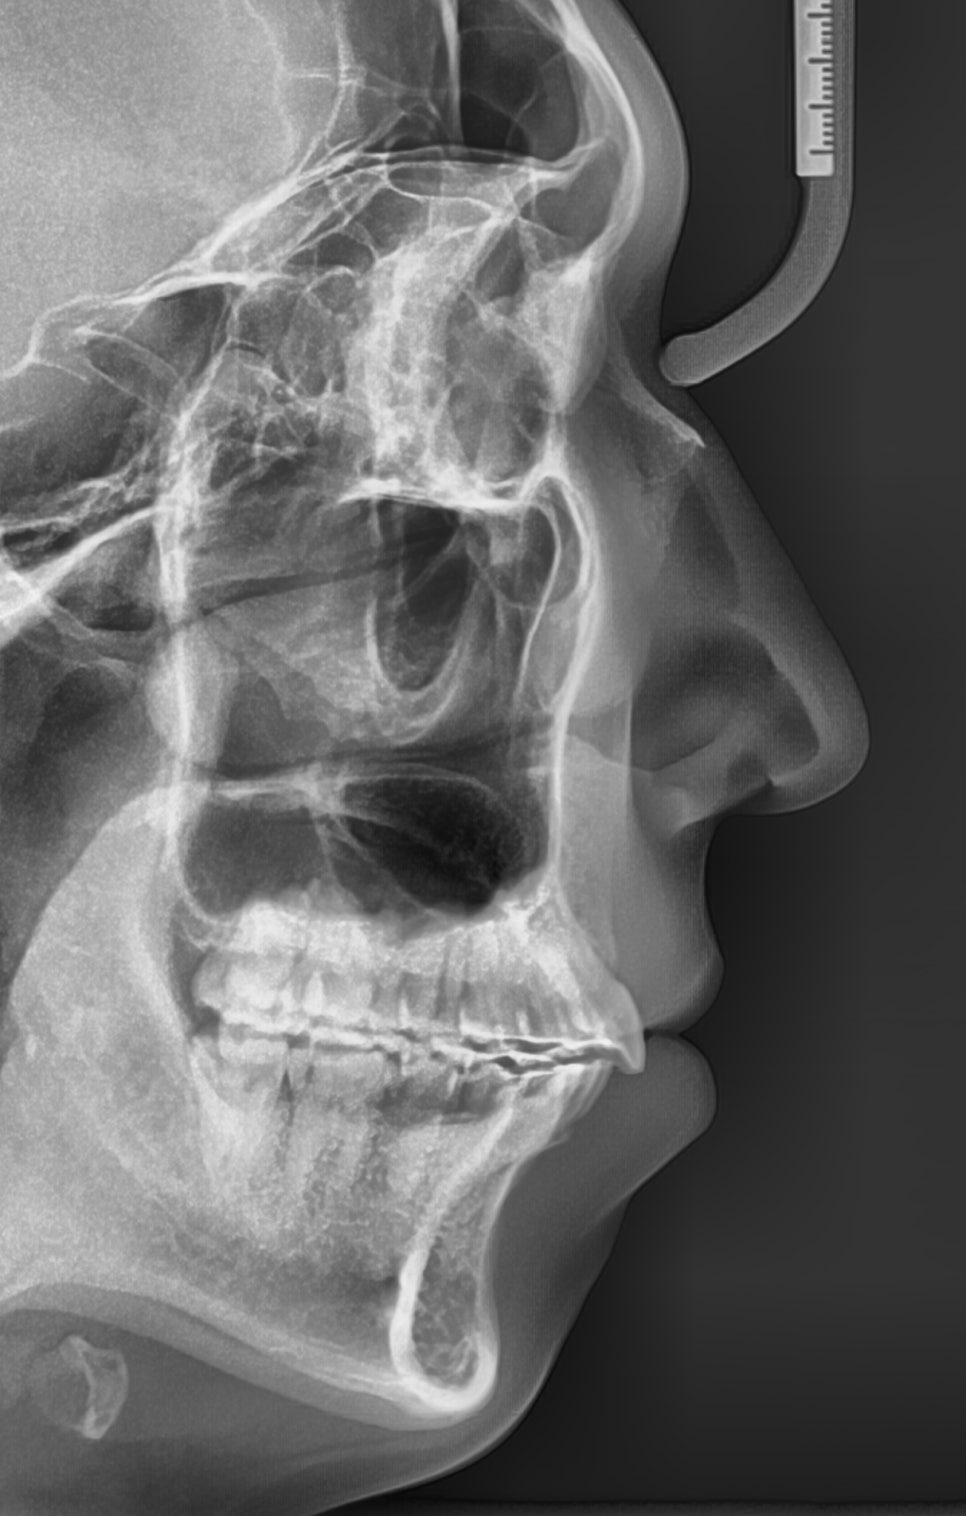

앞니가 많이 돌출되어 있는 환자분이었습니다.

어금니와 송곳니 관계를 보면 발치를 하는 것이 치료를 하는 입장에서 훨씬 편할 수 있는 상태였습니다.

환자분은 심한 무턱과 단안모의 형태를 가진 안모의 소유자였습니다.

드디어 교정 끝.

2019.8.30.에 저희 병원에 처음 오셨고 1달뒤 치료 시작

2022.9.27.에 치료 끝나셨으니 약 3년간 치료했습니다.

3년 중 약 2년반은 당기기만 했고, 오셔서 고무줄만 갈아끼고 가셨습니다.